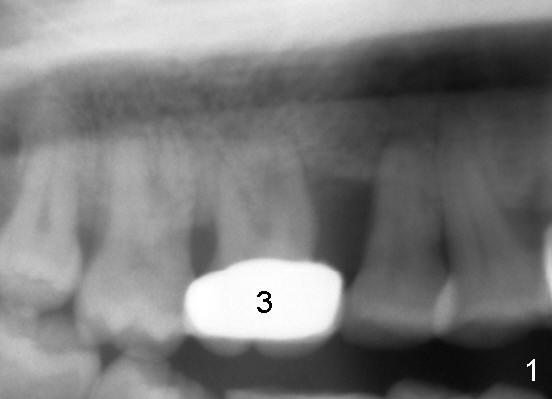

The tooth #3 of a 41-year-old lady is peirodontally compromised (Fig.1 (trimmed panoramus), 2 (PA)) with a large bony defect with the neighboring tooth (Fig.2 *). A large immediate implant is planned to be placed in the basal bone (7 or 8x17 mm, green box) to increase primary stability and reduce the amount of the bone graft to be used (Fig.3 (CT sagittal section),4 (coronal)). If the immediate implant is placed first, there is a limited space (Fig.3 arrows) to place bone graft (red circles) in the hidden areas. Therefore, it would be much easier to bone graft (mixture of autogenous bone, allograft and synthetic bone) first, packed tightly against the mesial, distal, buccal and lingual walls without blocking the entrance to the osteotomy just formed. In spite of the fact that the patient has severe periodontal disease, the bone density of the basal bone is high (Type I/III, Hounsfield units (500-1500)). Reamers will be used to create osteotomy and the autogenous bone will be saved and reused later on.